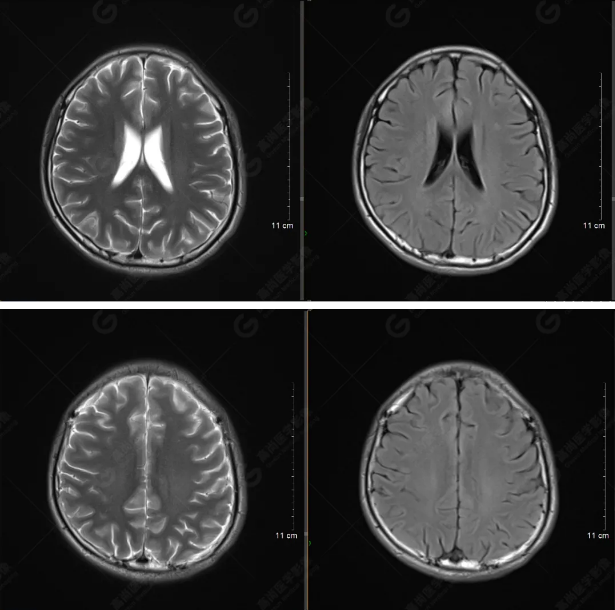

以下是平掃T2WI及FLAIR序列:

雙側(cè)大腦半球?qū)ΨQ,灰白質(zhì)對比正常,顱內(nèi)未見異常信號影。腦室系統(tǒng)未見擴(kuò)大,中線結(jié)構(gòu)居中。腦溝、裂未見增寬。幕下小腦、腦干未見異常。矢狀位示垂體形態(tài)、大小級信號未見異常。所示左側(cè)乳突內(nèi)見多發(fā)短T1長T2信號影。

顱腦MRI平掃未見明顯異常,左側(cè)乳突內(nèi)積血,建議補(bǔ)充SWI檢查。